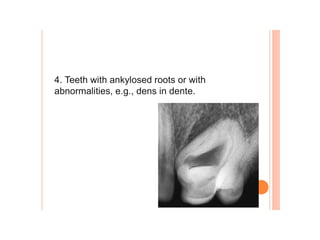

Dental caries, also known as tooth decay, is caused by certain types of acid-producing bacteria in the mouth that damage tooth structures when fermentable carbohydrates like sugar are present. It can lead to pain, tooth loss, infection, and in severe cases, death. While early signs may include white spots on teeth, untreated caries will form cavities. Risk factors include poor oral hygiene, frequent sugar consumption, dry mouth, and tobacco use. Treatment involves removing decay, restoring teeth, or extracting severely damaged teeth to prevent further destruction and infection. Preventive measures include proper brushing, flossing, limiting sugar intake, dental sealants, and fluoride therapy.